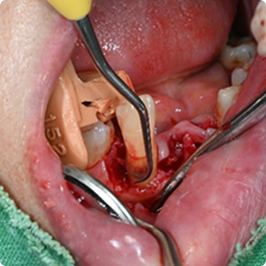

수술적 잇몸 치료 - 잇몸 수술

치아 뿌리 깊숙이 자리한 치석을 비수술적 치료만으로 제거하기 어려울 때,

잇몸을 절개해 직접 시야를 확보한 뒤, 숨어 있는 치석과 염증 조직을 깨끗이 제거하는 치료입니다.

엠도게인 치료 과정

• STEP 01

치주 치료로 잇몸염증 제거

• STEP 02

잇몸 절개 후 치아 뿌리 노출

• STEP 03

치아 뿌리 표면 깨끗하게 정리

• STEP 04

꼼꼼히 엠도게인 도포

• STEP 05

잇몸 봉합

• STEP 06

정기 검진으로 상태 확인